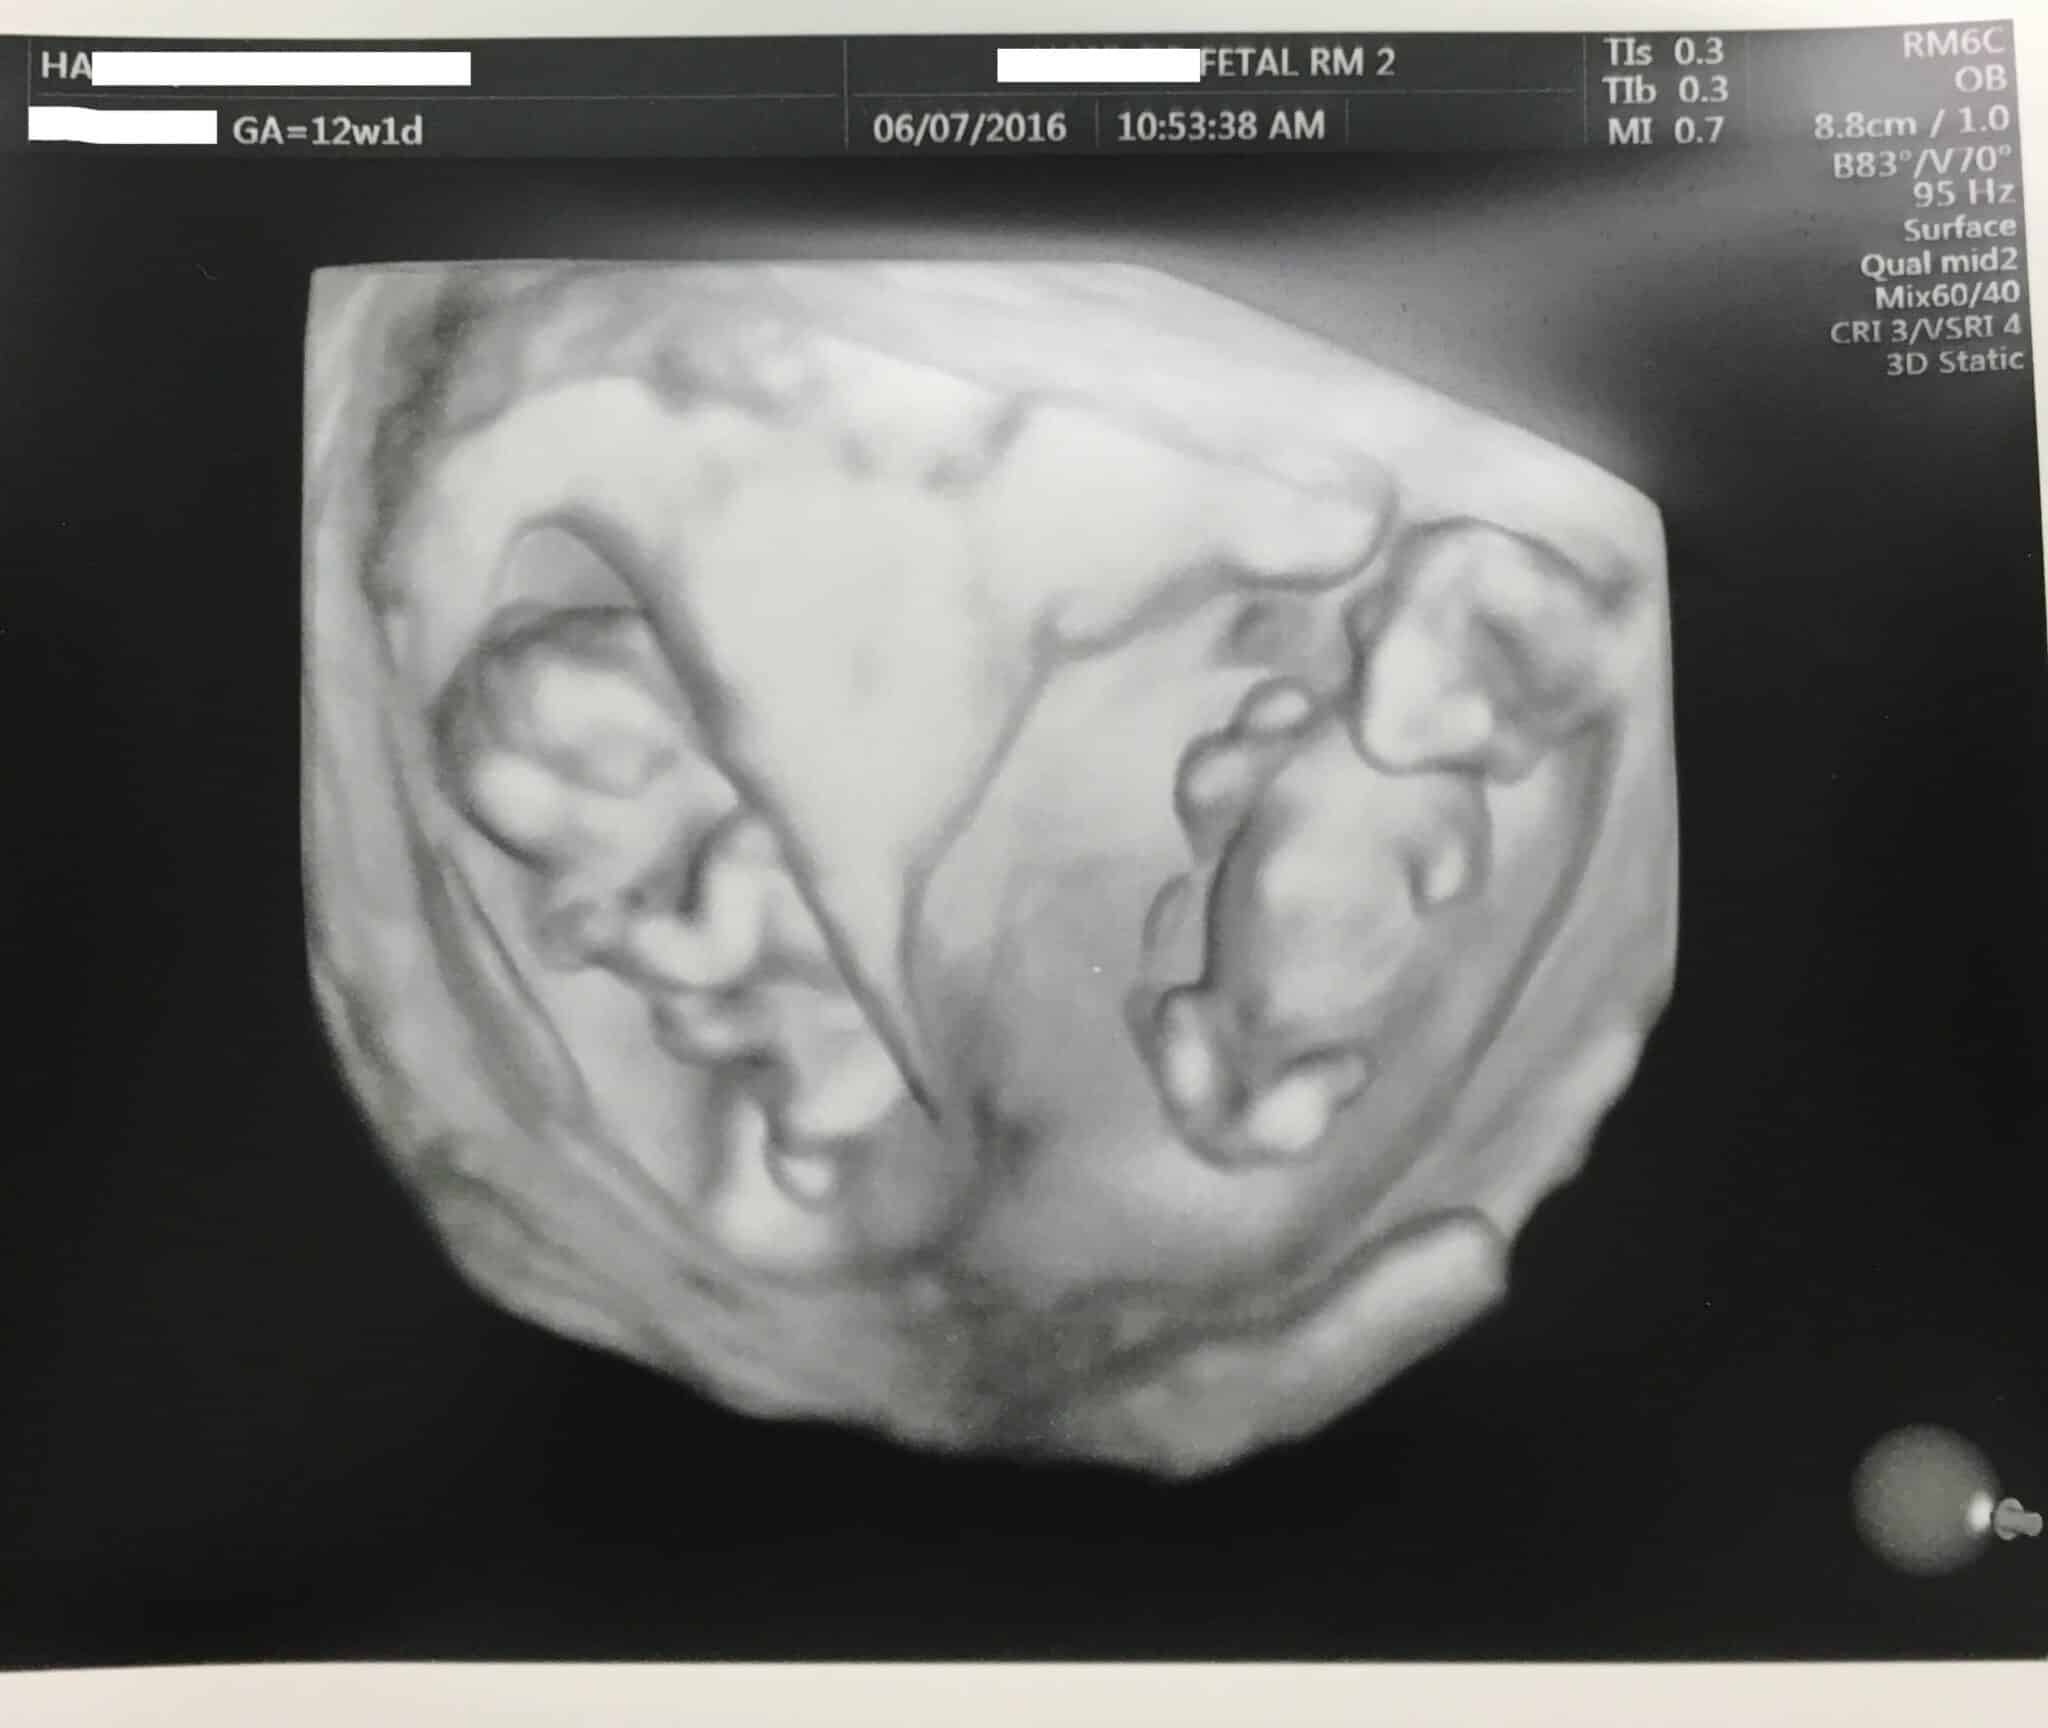

Ultrasound Photos at 12 Weeks Pregnant With Twins